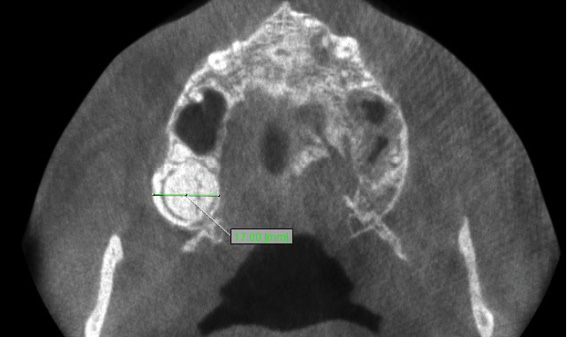

TITLE: Complex odontoma – a case report

STRESZCZENIE: Celem pracy jest przedstawienie przypadku zębiaka złożonego stwierdzonego u pacjenta leczonego ortodontycznie.

SUMMARY: The aim of the paper is to present a case of the complex odontoma found in an orthodontically-treated patient.

Zębiaki są najczęściej występującymi nowotworami łagodnymi pochodzenia zębowego. Obecnie uważa się je za zmiany hamartomatyczne utworzone przez przerost lub przejściowe zaburzenia w rozwoju tkanki zębowej (1, 2). Zębiaki najczęściej rozpoznawane są z użyciem rutynowych zdjęć rentgenowskich, ze względu na brak objawów klinicznych (3). Ocena histopatologiczna potwierdza diagnozę, szczególnie w przypadkach zębiaków złożonych, które mogą być mylone z kostniakami lub innymi wysoko uwapnionymi zmianami kostnymi (3-5).

Zębiaki są zazwyczaj tworami niewielkich rozmiarów (3, 4, 7). Wiek pacjenta w chwili rozpoznania to zwykle druga dekada życia, bez predylekcji do płci. Lokalizacja zmiany to częściej tylny obszar żuchwy (8).